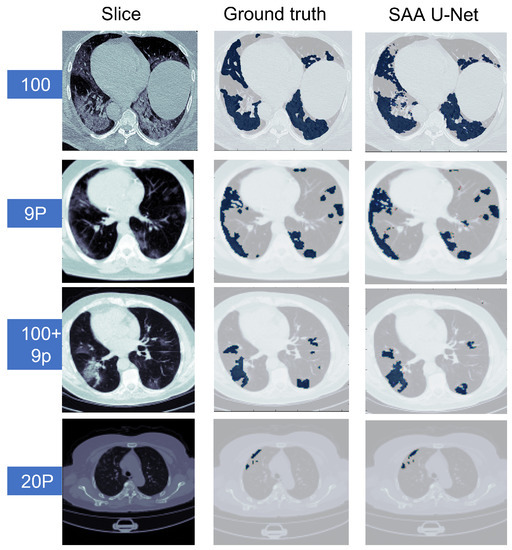

6.2. Binary Class Classification